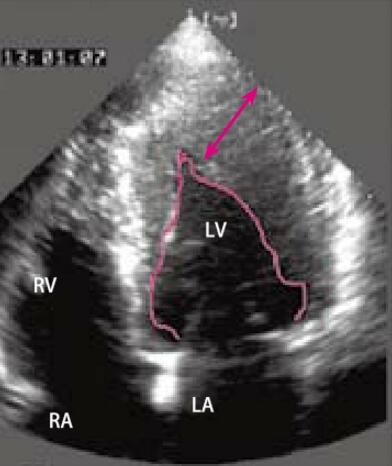

患者男性,27岁,体检行心电图检查(图4-7-1)。超声心动图示左室心尖段增厚(图4-7-2)。

图4-7-2 超声心动图 示左心室腔呈“A”字形